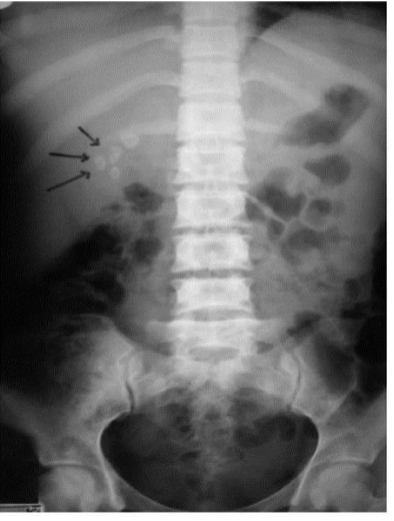

Calcified gallstones in gallbladder, cystic duct, and common bile duct

Porcelain (calcified) gallbladder

Chronic cholecystitis

Small risk for cancer